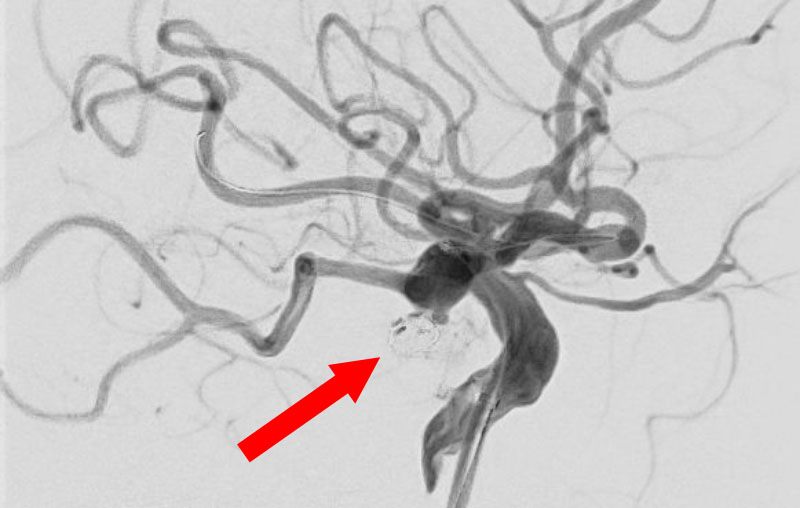

No.1631 手術前